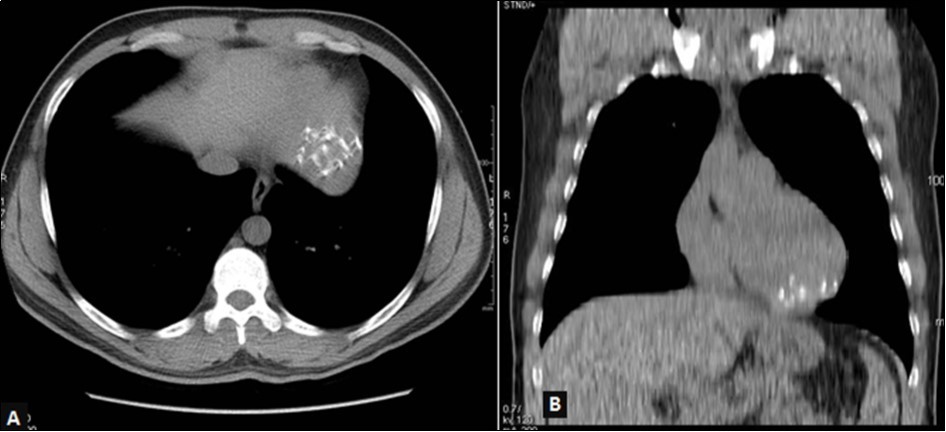

The 64-slice computed tomography (CT) showed a left ventricle intra-myocardial mass of tissue density (25 HU), not enhancing after injection of contrast, and containing multiple central and peripheral arciform calcifications (Figure 3,Figure 4,and Figure 5).

Figure 3.Thoracic CT without injection, mediastinal window, axial view (A) and coronal reconstruction (B): left ventricular mass with multiple calcifications in strata.